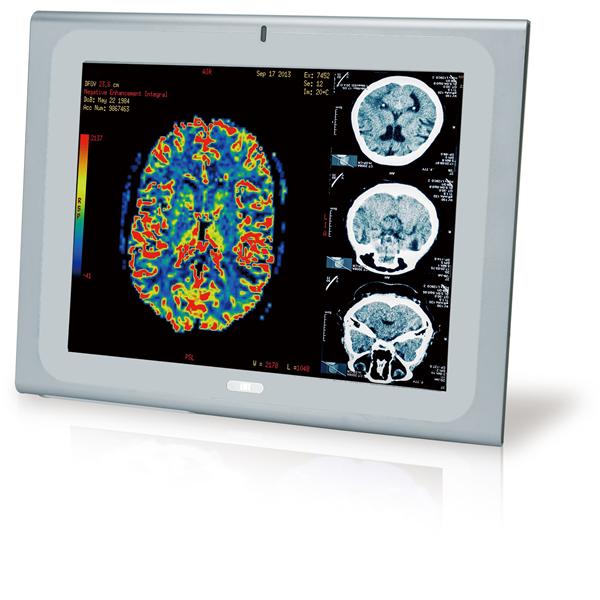

IEI Technology | Panel PCs 21.5" 250cd/m FH... |

IEI Technology | Panel PCs 17" Medical Pan... |

IEI Technology | Panel PCs 19" Medical Pan... |

IEI Technology | Panel PCs 17" Medical Pan... |

IEI Technology | Panel PCs 19" Medical Pan... |

IEI Technology | Panel PCs 17" Medical Pan... |

IEI Technology | Panel PCs 19" Medical Pan... |